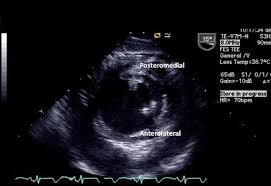

Label the Papillary muscles in the TG SAX Mid-Papillary TEE view

Label the Papillary muscles in the Mid Commissural View

1. Anterolateral

2. Posteromedial